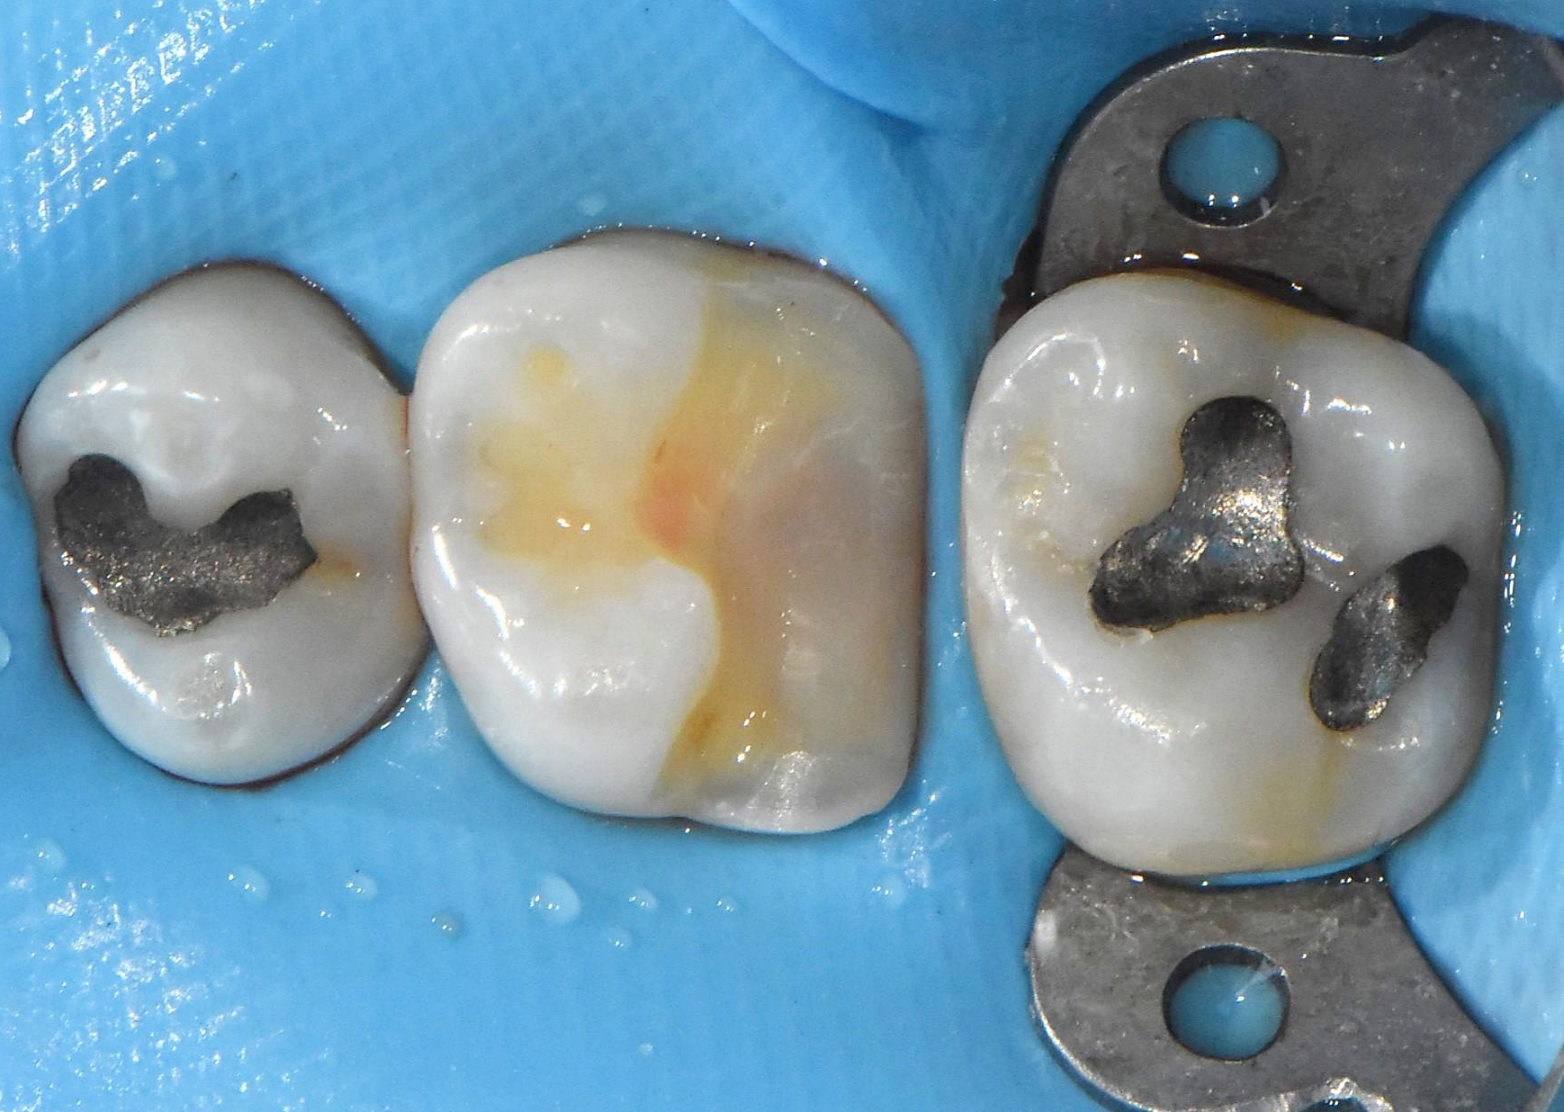

일상생활 중 앞니 끝이 살짝 깨지는 사고는 빈번하게 발생합니다. 이때 무작정 치아를 다듬고 라미네이트나 올세라믹 크라운을 씌우는 대신, 파절된 부위만을 고강도 레진으로 층층이 쌓아 올리는 '레진 빌드업(Resin Build-up)'을 적용하면 치아 삭제를 0에 가깝게 줄일 수 있습니다. 본원의 임상 사례에서도 볼 수 있듯, 인접 치아의 투명도와 질감을 그대로 재현하여 티 나지 않는 심미적인 복원이 가능합니다. 어금니의 오래된 아말감 교체 역시 마찬가지로 건강한 치질은 남기고 레진을 이용해 본래의 해부학적 형태를 섬세하게 재건합니다.

이처럼 최소삭제 접착 치료는 자연치아를 보존하는 최선의 방법이지만, 술자의 고도의 테크닉과 철저한 환경 통제가 수반되어야만 성공할 수 있습니다. 특히 치과용 접착제는 타액(침)이나 혈액, 입김의 수분에 노출될 경우 접착력이 급격히 저하되어 보철물 탈락이나 2차 충치로 이어집니다. 따라서 파란색 고무막인 '러버댐(Rubber Dam)'을 장착하여 치료 부위를 100% 격리하는 방습 과정은 절대 생략해서는 안 되는 필수 원칙입니다.